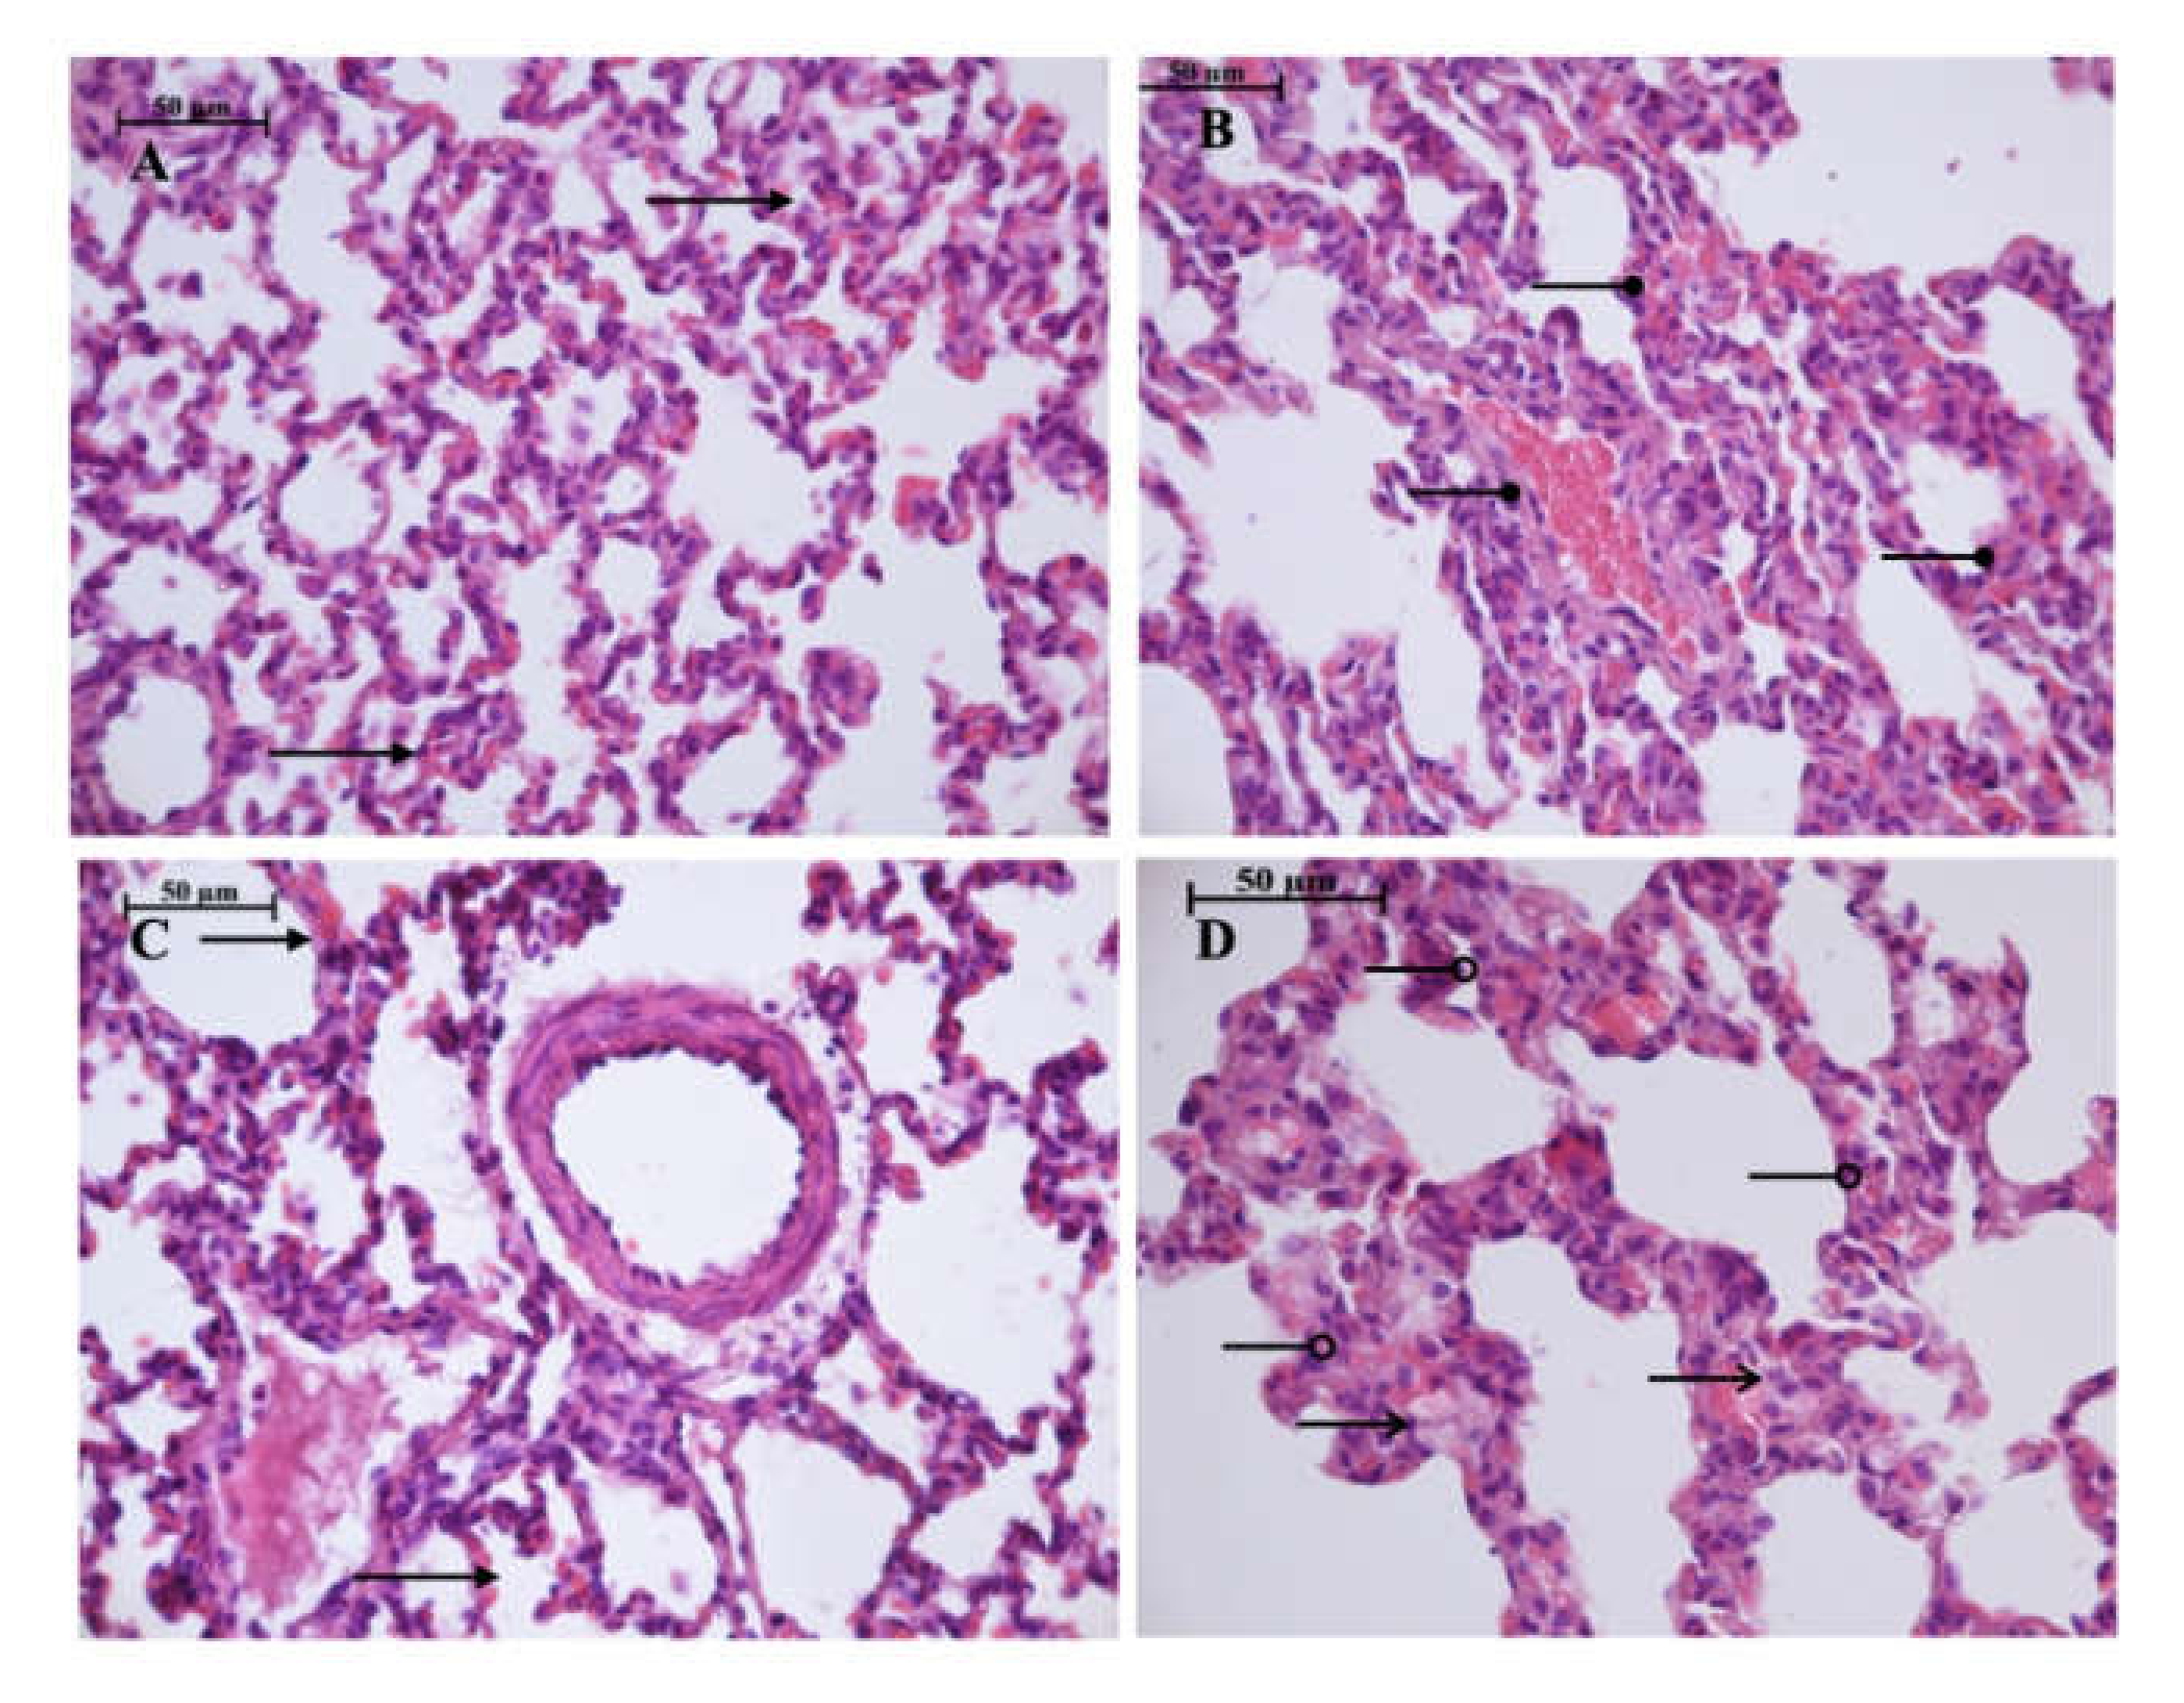

Light microscopy revealed disturbances of myocardial structure, increase in the distance between the discs, and a lack of cross-striations in the hibernation area. We observed less intense damage in HHP animals compared with the control group (Figure 3). We found reversible (segmental contractions of I and II degree) and irreversible (disintegration of myofibrils, segmental contracture of III degree) changes in myofibrils. Predominantly reversible changes were found in the HHP group. Light microscopy of kidneys revealed marked edema of cortical and medullar substances in the control group (Figure 4). Gut mucosa and lungs had enlarged capillaries, sometimes filled with erythrocytes (Figure 5 and Figure 6). Light microscopy of gut mucosa, lung parenchyma, and kidneys were less affected in the HHP group.

Figure 6.

Light microscopy of the lung parenchyma. HHP group (A): moderate hyperemia (

) of the interalveolar capillaries, 400×, H&E; Control group (B): enlarged capillaries (